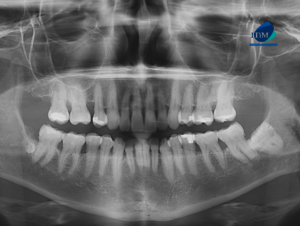

Paciente masculino de 8 años de edad acude al Instituto de Diagnóstico Maxilofacial – IDM (Miraflores) para evaluación imagenológica.En la radiografía panorámica (Figura 1), se